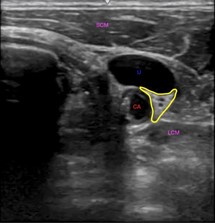

The rationale for the use of SGB for RVA lies in decreasing sympathetic effects on the heart. The stellate ganglion is located lateral to the vertebral bodies of C6-7. It lies anterior to the longus colli muscle and in close proximity to the internal jugular vein and common carotid artery (Figure 1). The stellate ganglion provides the majority of the sympathetic input to the ventricles [7]. Cardiac arrest and shocks cause myocyte injury resulting in an endogenous catecholamine surge. This coupled with repeated doses of epinephrine increases the likelihood of repeated arrhythmia [2,6]. By interrupting impulses between the stellate ganglion and the heart, sympathetic tone and corresponding arrhythmic effects are decreased, providing a more favorable environment for sustained normal rhythm.

Figure 1: Transverse ultrasound image of the lateral neck showing the stellate ganglion outlined in yellow, the carotid artery (CA) labeled in red, the internal jugular vein (IJ), labeled in blue and the longus colli (LCM) and sternocleidomastoid (SCM) muscles labeled in purple.